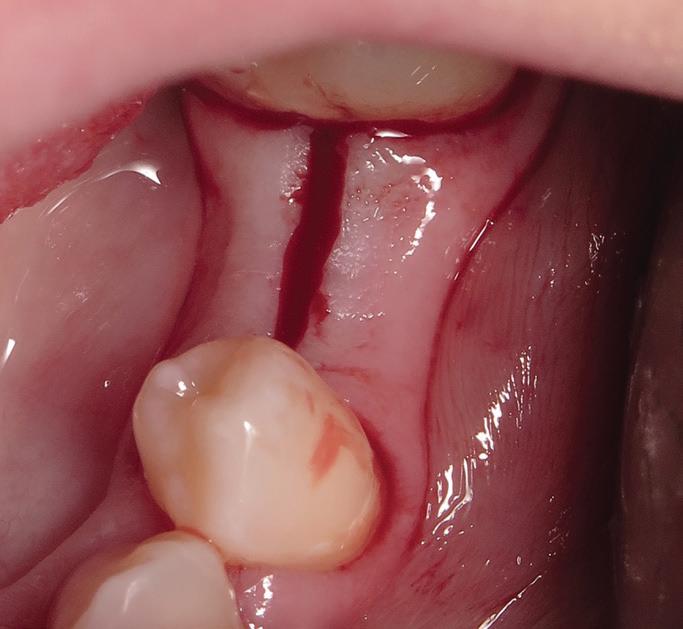

Root migration after coronectomy of impacted mandibular third molars: case reports

Jéssica Lemos Gulinelli

Pâmela Leticia dos Santos